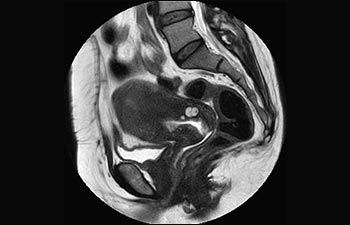

La Sra. Silvia Schiffer, directora y radióloga experta en la clínica Radiologie Schiffer, en Alemania, comparte sus experiencias con el sistema de RM Prodiva 1.5T.